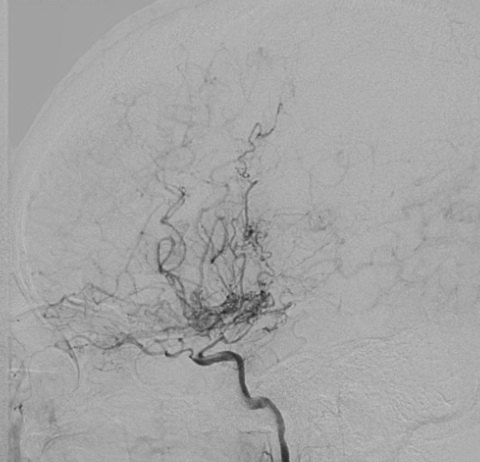

moyamoya病,仅凭一层ct图像即可确诊的疾病_血管_诊断_yoon

【影像病理】烟雾病(moyamoya disease),ct及mri表现